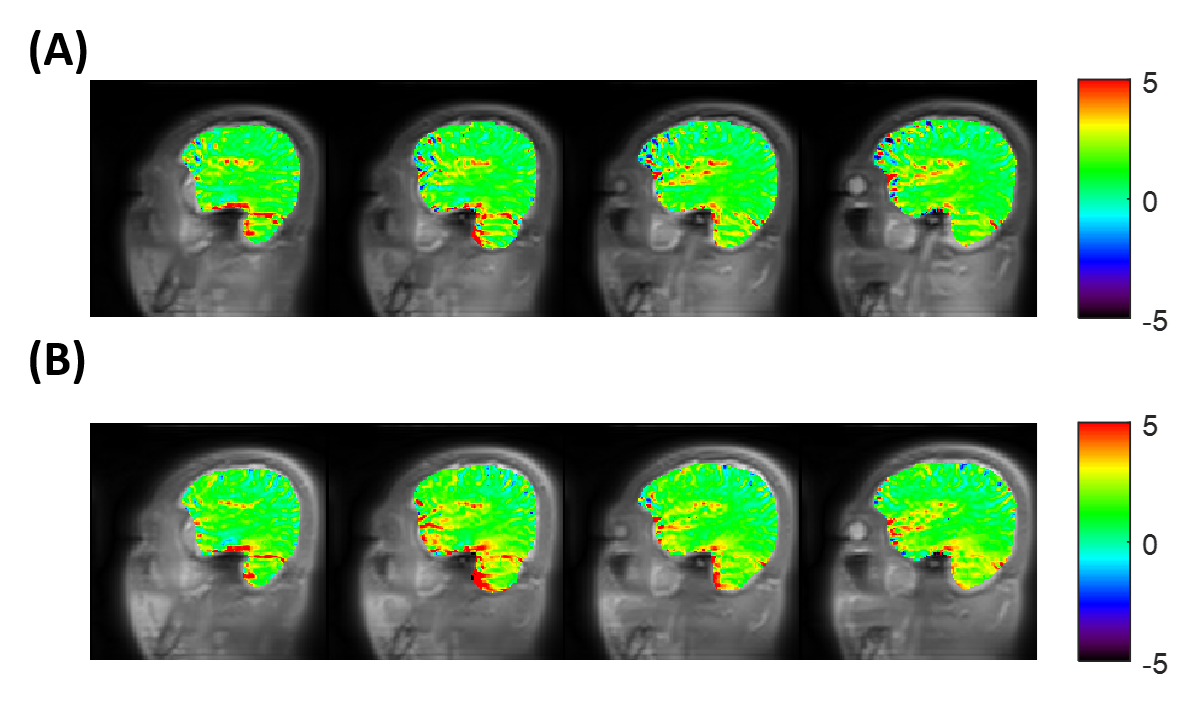

Fig. 1A shows the elliptical k-space trajectory with centric reordering, where the color marks a center-to-periphery echo order. Fig. 1B shows the portion of the k-space filled by one shot, and the other shots are rotated versions of this illustrated one. Fig. 2 illustrates the optimization results of different objective functions. When only optimizing SNR, the proposed model generated a signal curve similar to the constant 120° case (Fig. 2B), but with much smaller flip angles (Fig. 2A) and 6.1% smaller full width at half maximum (FWHM) of PSF (Fig. 2C). When only targeting spatial resolution, the proposed model yielded a constant signal curve during the majority of the echo train (Fig. 2E), leading to a PSF close to the ideal one (Fig. 2F). When optimizing both SNR and spatial resolution, the optimized flip angles yielded both 6.1% higher signal (Fig. 2H) and 12.1% smaller FWHM (Fig. 2I) than the constant 120° case. Fig. 3 shows the measured SNR across several slices in a normal volunteer, where the optimized flip angle in Fig. 2G yielded SNR consistently higher than the original constant FA case. The APTw maps revealed no visual distinction between the two FA schemes (Fig. 4).

Figure 4. APTw maps of several slices from the two FA schemes in a healthy volunteer: (A) Conventional constant 120°; (B) Optimized variable flip angles. There is little difference between these two sets of APTw maps.